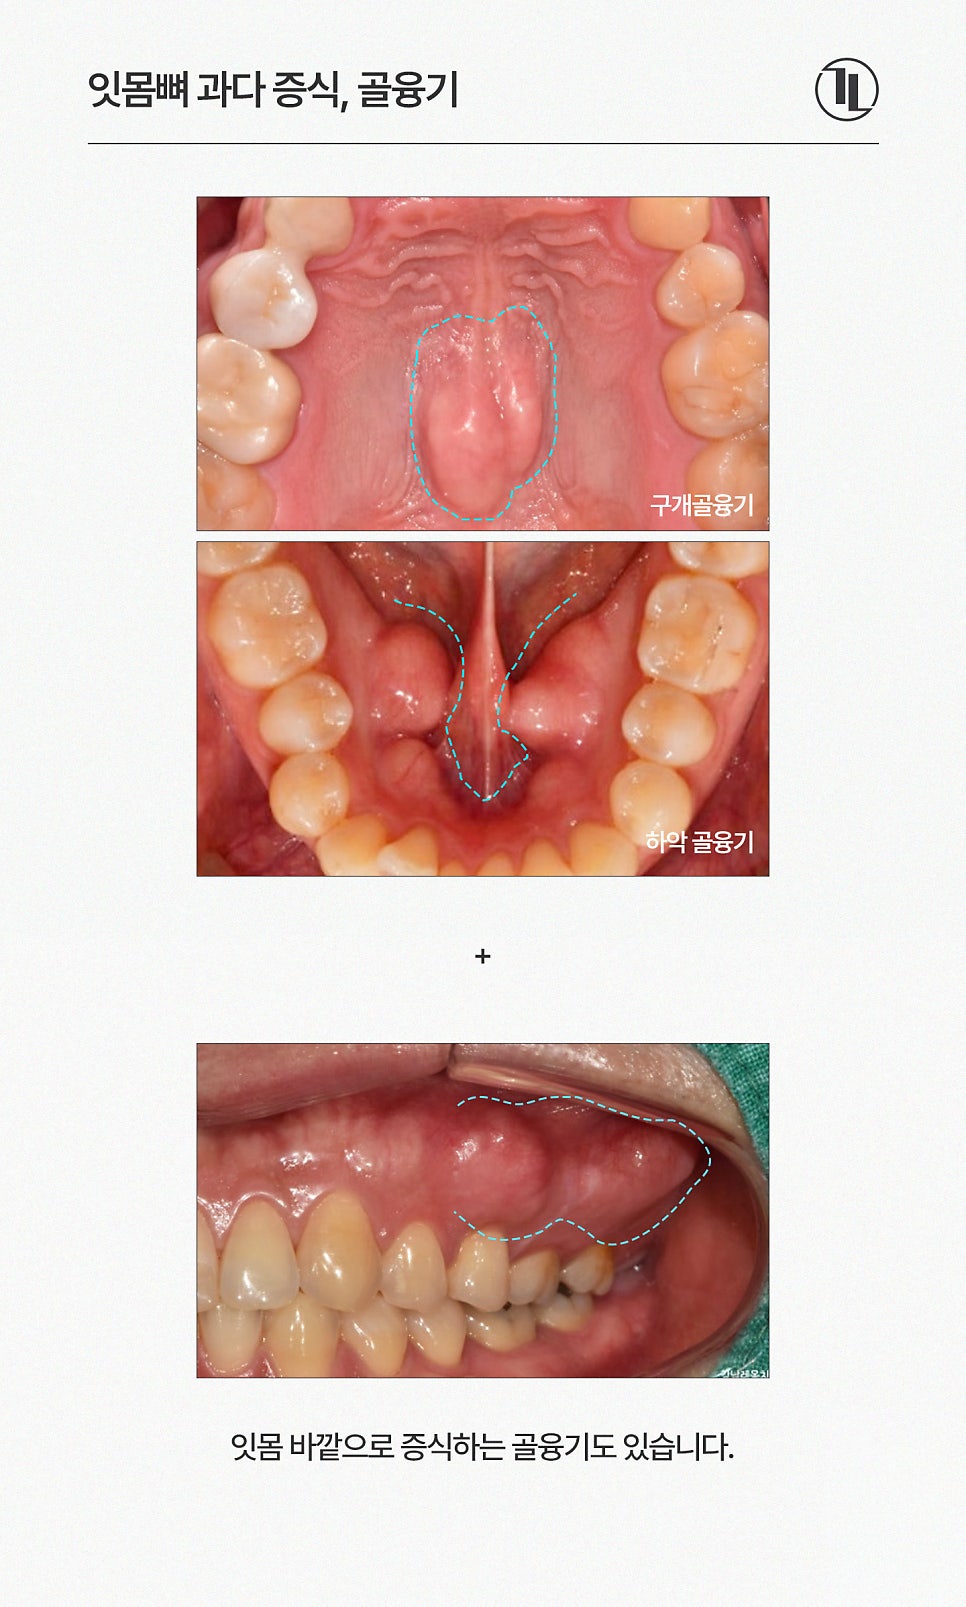

✔ 하악골융기

위치: 혀 아래쪽, 아래 어금니 안쪽 잇몸 부위

특징: 좌우 대칭적으로 발생하며

육안으로는 잇몸이 약간 부풀어 보입니다.

✔ 구개골융기

위치: 입천장(구개) 중앙 부위

특징: 입천장 가운데 돌출된 단단한 혹

하악골융기와 구개골융기로 구분됩니다.